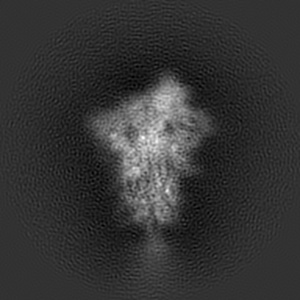

Spike_GSAS_6P and R1-32 Fab with 3to1 ratio

Single-particle4.75 Å

Sample: SARS-CoV-2 S-GSAS/6P spike trimer bound to R1-32 Fab with 3:1 ratio